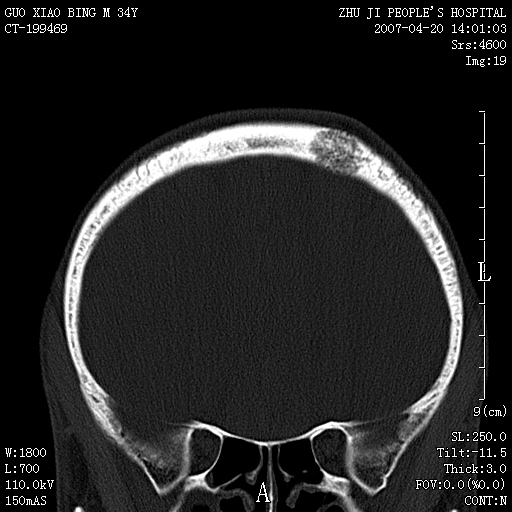

以下是引用qiuleiyu在2007-4-27 16:41:00的发言:[br]ct左侧额顶部囊性膨胀性骨质破坏,边缘有轻度硬化,其内示多发点条状高密度。[br]mri;t1低信号,t2明显高信号。界清。增强后明显强化。[br]综合考虑;颅内血管瘤。上传该病例,目的在于加深印象,共同学习。[br]骨血管瘤好发于颅骨及椎体。为良性肿瘤。组织学上分海锦型及毛细血管型。前者多见。[br]颅血管瘤典型影像学表现;[br]1,平片;类圆形骨质破坏,边缘硬化,内示中央向周边年轮状辐射(残存增粗骨小梁)。[br]2,ct;颅内板障内膨胀骨质破坏,边缘硬化,内示密集点状及放射状骨针影。[br]3,mr;t1、t2高信号。该病例t1不高可能与血流较丰富有关。边缘低信号。增强明显强化。[br]鉴别;[br]1,脑膜瘤;主要累及内板,与血管瘤发生于板障不同。颅板骨质增生硬化,与颅内垂直放射状骨针。与血管瘤日光放射状不同。增强可见脑膜尾征。[br]2,嗜酸性肉芽肿;起自板障溶骨性骨质破坏。内无点状及放射状高密度影。边缘硬化不明显。局部可有骨膜反应。[br]3,转移性肿瘤;溶骨破坏边缘模糊,无硬化边。发展迅速。有原发肿瘤史。可多发。可出现软组织块。[br]4,单发骨髓瘤;发病年龄较大,临床可能全身骨质疏松,骨痛。免疫球蛋白增高。部分病例本周氏蛋白可增高。可有边缘硬化,然内无点状高密度影。[br]